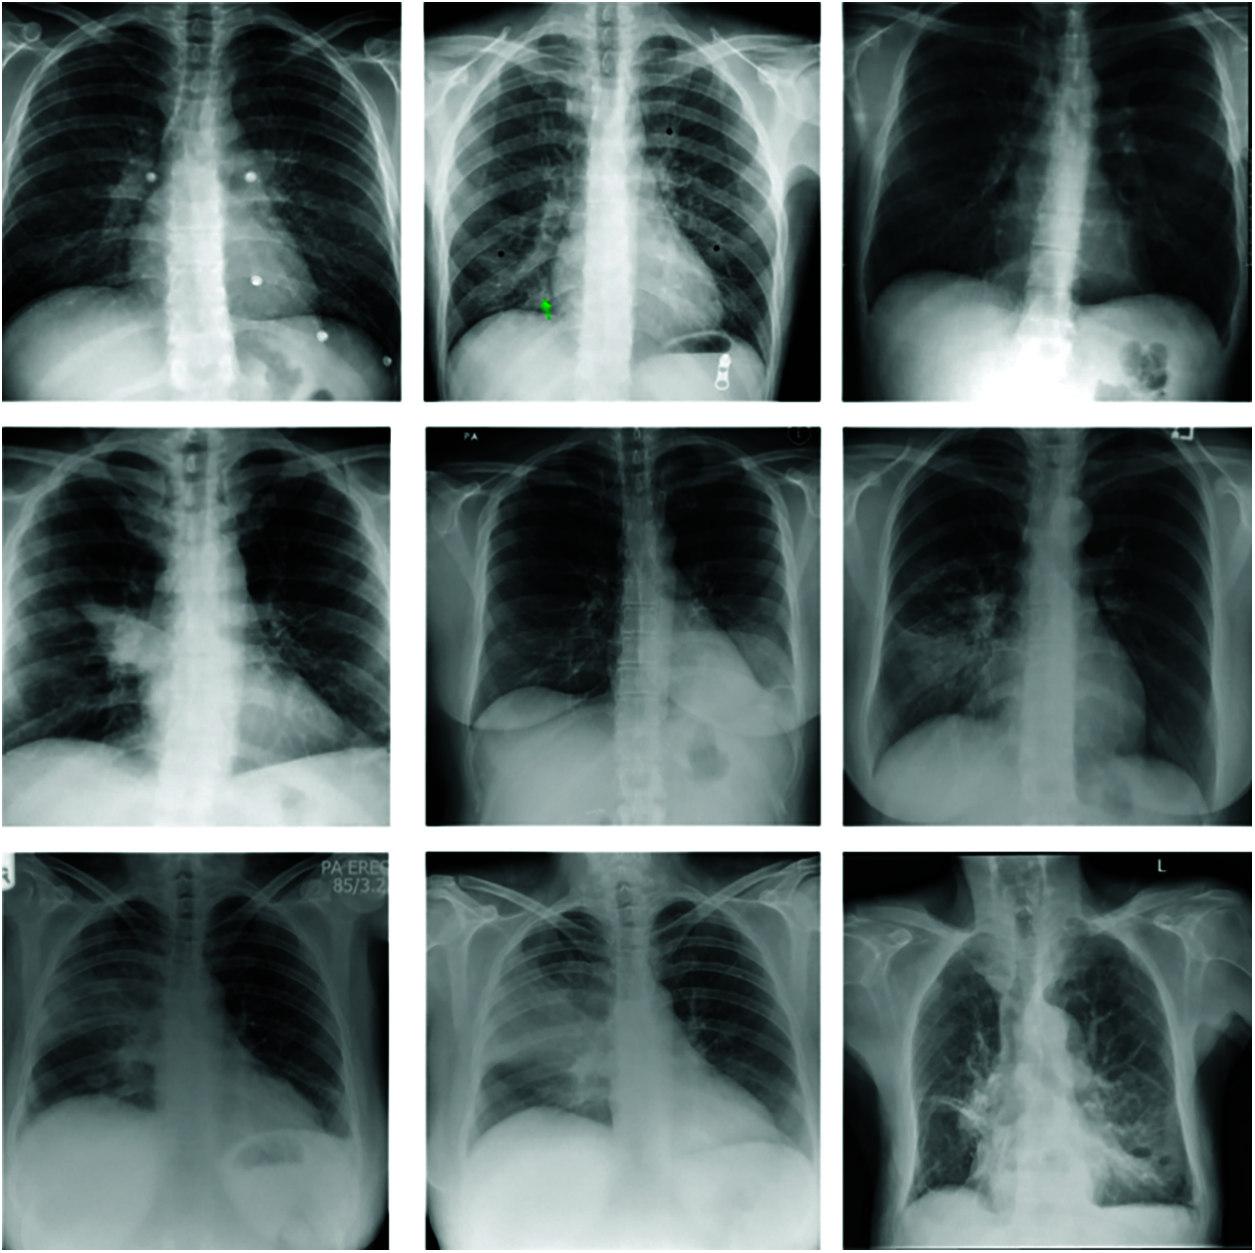

For our experimentation, we mainly used the public dataset obtained from a worldwide collection by Cohen et al. [25]. This dataset consists of chest X-ray and CT images of patients which are positive or suspected of COVID-19 (Figs. 3, 4) or other viral and bacterial pneumonias (MERS, SARS, and ARDS.). Data are collected from public sources as well as through indirect collection from hospitals and physicians [26]. This dataset currently consists of around 504 X-Ray images of COVID-19 positive patients and total 866 images. The GitHub repository associated with the work collects images from websites such as radiopaedia.org, sirm.org, eurorad.org and coronacases.org. It is also open for contributions and all new images are rigorously annotated following Posterior Anterior (PA), Anterior Posterior (AP) and Anterior Posterior Supine (AP Supine) views of the lungs. Additional patient information is also provided such as: patient id, Number of days since the start of symptoms, sex, age, type of pneumonia, RT_PCR_positive, survival, if the patient was intubated , if the patient was in the ICU (intensive care unit) or CCU (critical care unit), if he needed supplemental O2, if the patient was successfully extubated, temperature, pO2 saturation, leukocyte_count, neutrophil_count, lymphocyte_count, modality (CT, X-ray, or something else), Date on which the image was acquired, ‘Hospital name, city, state, country’, the filename, Digital object identifier (DOI) of the research article, URL of the paper or website where the image came from, the license of the image such as CC BY-NC-SA, ‘clinical notes and other notes’). The data in image form that is used to train our model are presented in Tab. 1.

Figure 3: Images X-ray without covid-19